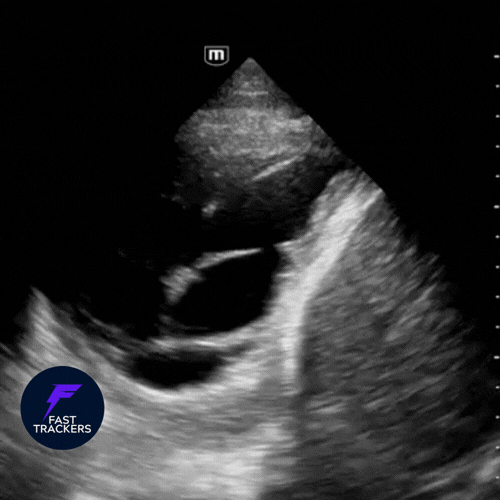

🫁 Consolidation (syndrome alvéolaire)

Substitution de l’air alvéolaire par du liquide ou de l’inflammation : le parenchyme prend un aspect tissulaire (« hépatiforme »).

Signes échographiques

- Aspect tissulaire : zone échogène, granuleuse, proche de l’aspect du foie.

- Bronchogrammes aériques : air circulant dans les bronches visibles au sein d’une condensation.

- Bronchogrammes dynamiques : signal Doppler couleur avec la respiration → pneumonie (voies aériennes perméables).

- Bronchogrammes statiques : immobiles → atélectasie (obstruction bronchique).

- Poumon “déchiqueté” : limite irrégulière entre le poumon aéré et la consolidation.

- Épanchement pleural associé fréquent, souvent visualisé comme une lame anéchogène au-dessus du diaphragme.

Étiologies courantes – Pneumonie, atélectasie, aspiration, contusion pulmonaire.